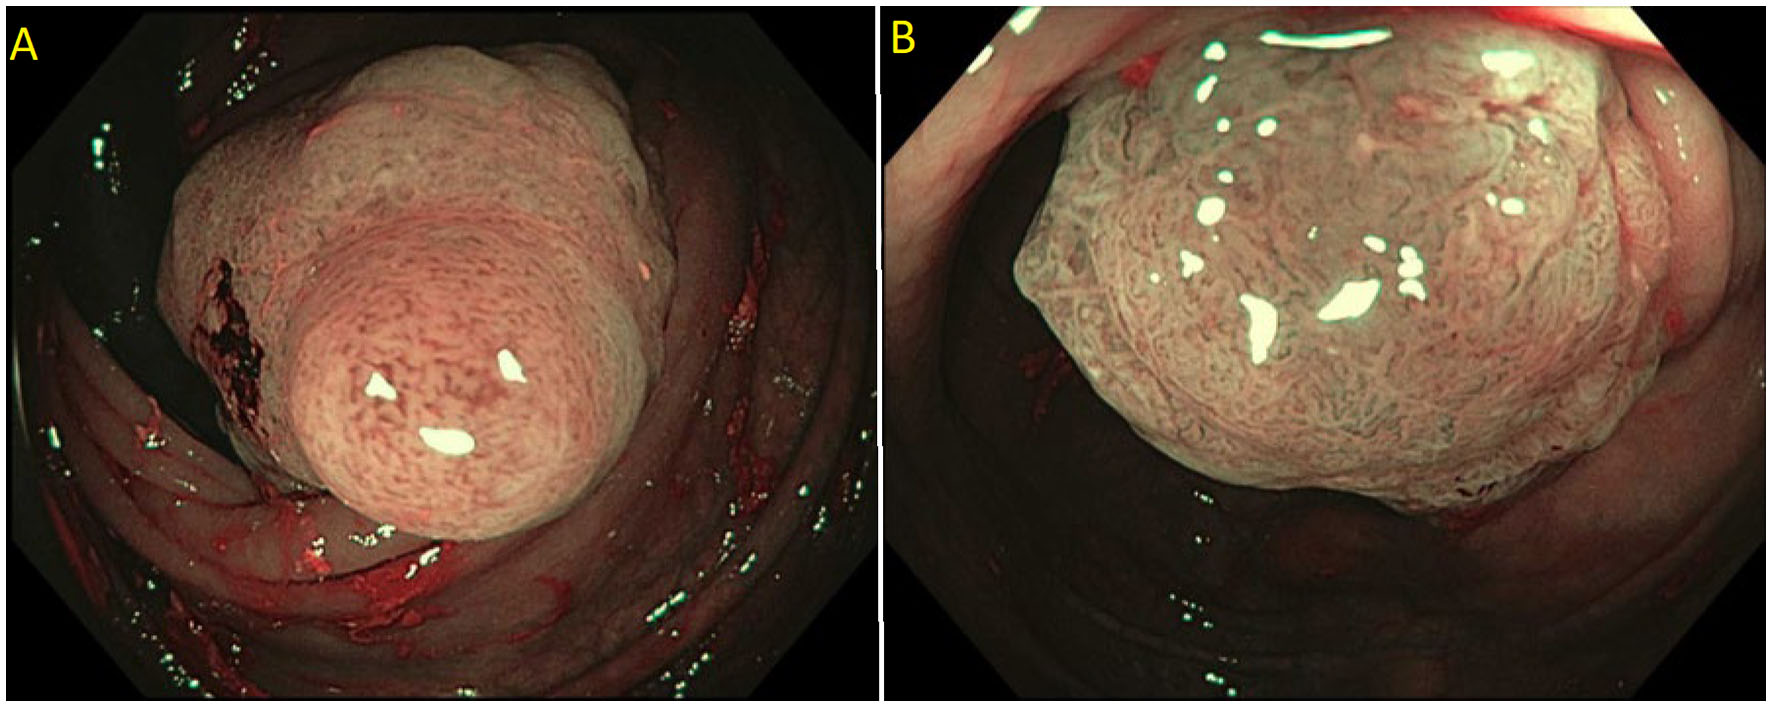

Detailed endoscopic assessment of a lesion with high-definition imaging is a critical first step for the optimal management of colorectal polyps. However, high-definition white light evaluation alone for features such as fold convergence, edge retraction, expansion/thickened folds, firm consistency, erythema is not enough for an assessment of SMIC. Increasing size, recto-sigmoid location, and surface morphology have been associated with an increased risk of SMIC (34–36). Lateral spreading lesions (LSL), polyps that spread laterally and circumferentially rather than vertically, are commonly seen in practice (Figure 1). These lesions can be large and technically challenging to remove due to size, location, and fibrosis. The frequency of invasive cancer in homogeneous granular lateral spreading lesions (G-LSL) tends to be lower (<5%) than for G-LSL with a dominant nodule and for non-granular LSL (NG-LSL), which are flat or pseudo-depressed, as well as large sessile and bulky lesions of similar size (Figure 2) (35, 37).

Figure 1

(A) Granular lateral spreading lesion; (B) Granular lateral spreading lesion with dominant nodule; (C) Non-granular lateral spreading lesion. These lesion have a higher risk of fibrosis and invasive cancer. Polyp was tubular adenoma; (D) Non-granular lateral spreading lesion on white light; (E) Non-granular lateral spreading lesion on Narrow Band Imaging (NBI). Histology revealed a T1 adenocarcinoma.